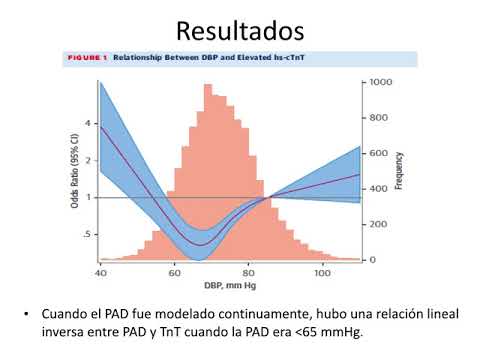

Presión arterial diastólica, daño subclínico y eventos. Dra. Carolina Pappalettere. Residencia de Cardiología. Hospital C. Argerich. Buenos Aires